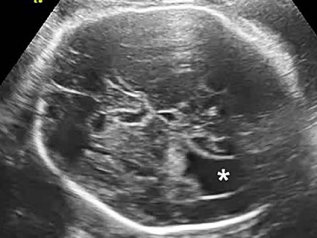

(2)检查内容

主要观察能显示的胎儿重要器官的形态结构,包括:胎儿的小脑、侧脑室、上唇部、脊柱、严重的腹壁缺损胸腹脏器外翻、肾脏、胃泡、膀胱、股骨肱骨胫腓骨尺桡骨、四腔心等。在妊娠期间,每位胎儿都要做32~39个切面检查。